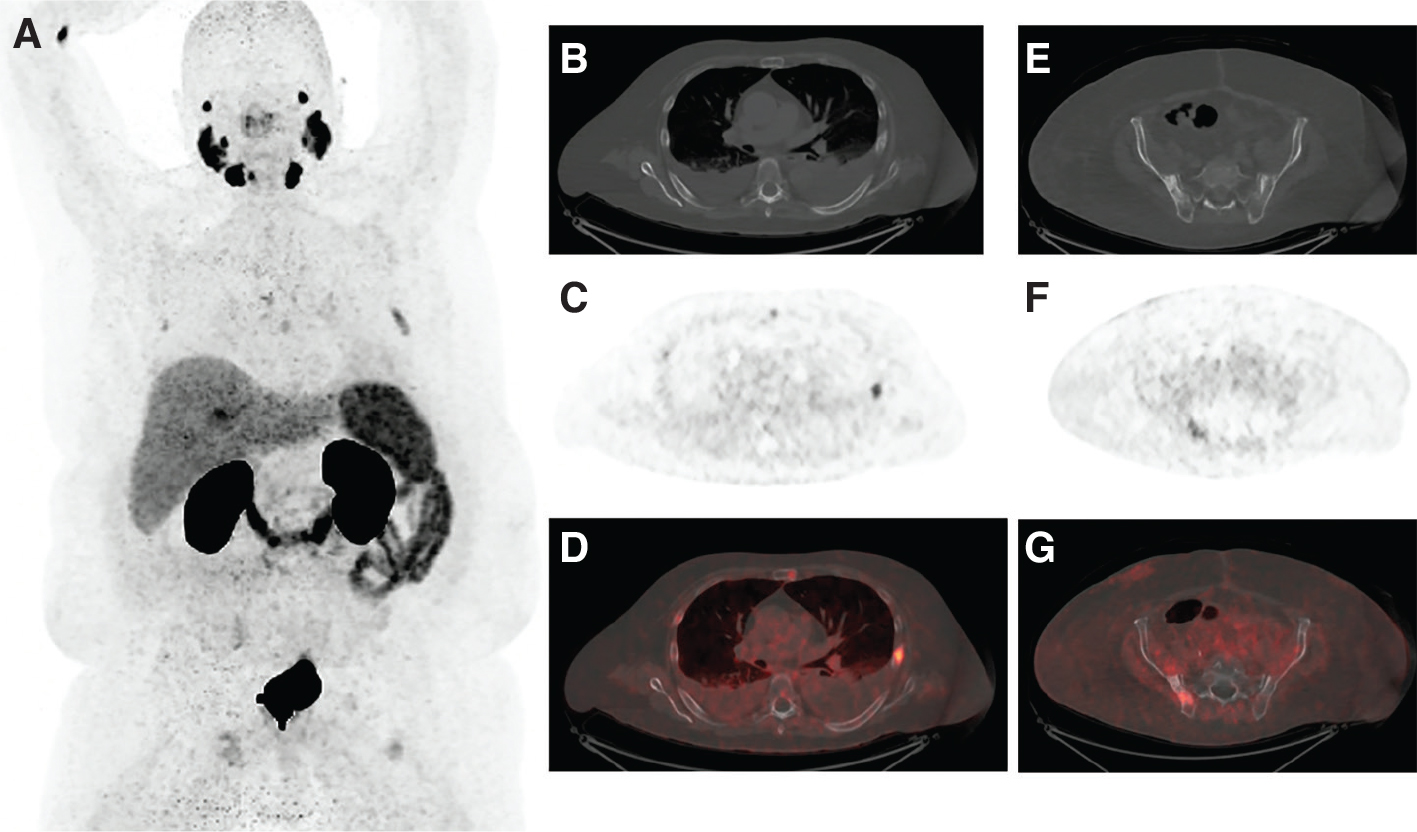

Fig 1

Figure 1. An 89-year-old male with mCRPC eligible for 177Lu-PSMA-617. A, Maximum intensity projection (MIP) image from a PSMA PET scan showing intensely PSMA-avid mediastinal and retroperitoneal lymphadenopathy, as well as intensely PSMA-avid metastatic lesions in the liver and lumbar spine. B, Fused axial image more clearly demonstrating extensive PSMA-avid retroperitoneal lymphadenopathy. C, Fused axial image more clearly demonstrating intensely PSMA-avid liver metastases. D, Fused sagittal image showing PSMA-avid osseous metastases in the lumbar spine.